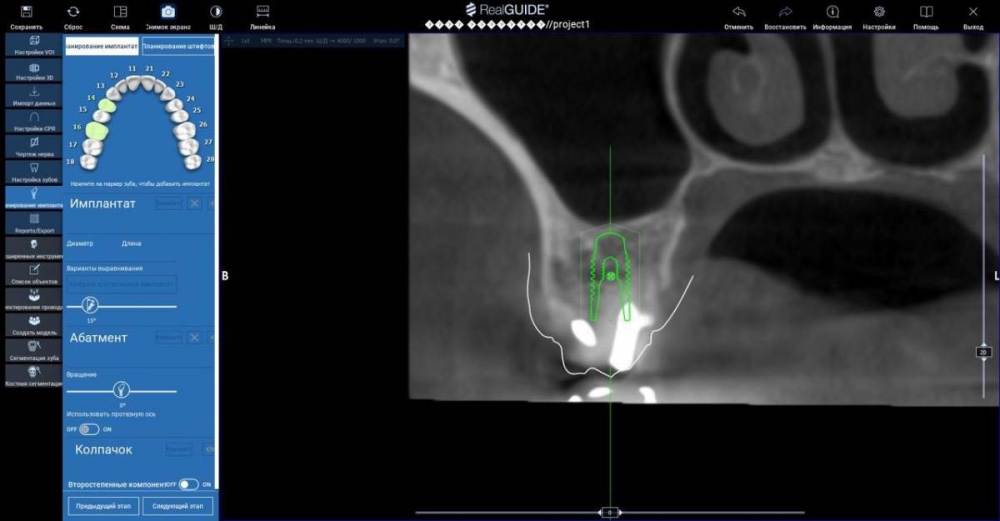

TIGER Опубликовано 11 августа, 2022 Поделиться Опубликовано 11 августа, 2022 Всем ? привет!закрытый синус через нави (шаблоны изготавливаю сам)и под контролем скопа,посадка на 12 часов всегда.и важно имплант с неагрессивным апексом ,преп ложа- проламывание дна фрезами DENSAH на реверсе 9 1 Ссылка на комментарий